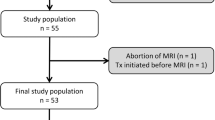

A total of 155 patients with MM were referred by the hospital hematology service at our institution to whole-body reduced MDCT in our department. Of these, 20 patients had to be excluded because of a history of cancer with bone metastases, spinal fractures and surgery including osteosynthesis and vertebroplasty, history of radiotherapy, or metabolic disease with bone involvement. Another 25 patients had to be excluded because the CT examination was performed with single-energy and/or no current in-house hematologic laboratory surveillance. Consequently, 110 patients (63.0 ± 11.0 years, 51 female) with MM who underwent whole-body DECT for staging before therapy were included. The clinical characteristics are shown in Table 2. Of this patient cohort, a subgroup of 56/110 patients (63.9 ± 11.8 years, 24 female) who had been currently diagnosed by bone marrow biopsy was separately analyzed (Fig. 2). These patients were primarily staged as stage I (n = 16, 28.6%), II (n = 10, 17.9%), and III (n = 30, 53.6%) MM.